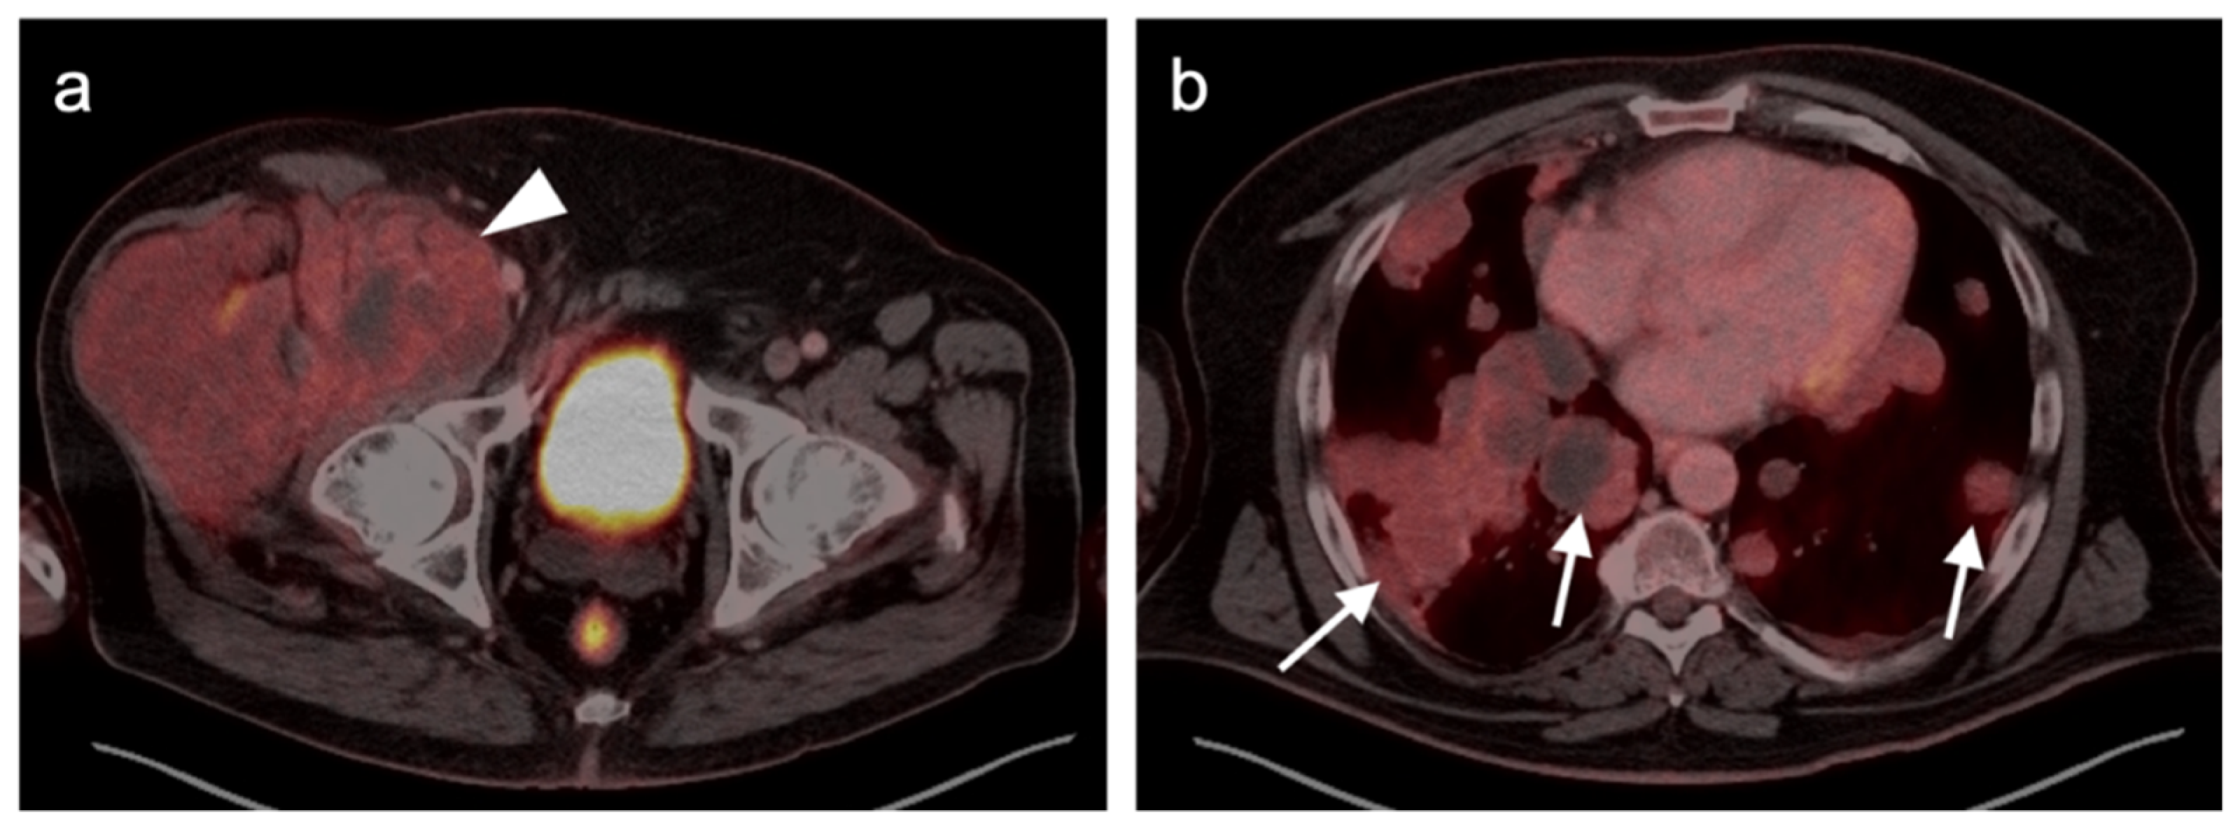

3. Sarcomas

3.1. Soft Tissue Sarcomas

3.1.1. Undifferentiated Pleomorphic Sarcoma

3.1.2. Leiomyosarcoma